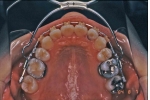

クリアリテーナー

プレス機プレス直後ハサミで切断完成通常のリテーナーは、0.8-0.9mmくらいのワイヤーが歯の表面を覆っているので、審美性をより考慮する場合は別の選択をする場合もあります。近年は、プラスティックの素材が非常に進化してきているので、かなり薄く加工してもそれなりの強度が得られるようになってきました。そこで、歯の表面を薄い透明なプラスティックで、密着する形で全部覆ってしまうタイプのリテーナーが好んで使用されています。このタイプを「クリアリテーナー」と言います。

多くの可撤式装置は、レジンというプラスティック素材を重合硬化させて作製するのですが、この装置は専用のプレス機を用いて圧着成形で作製します。